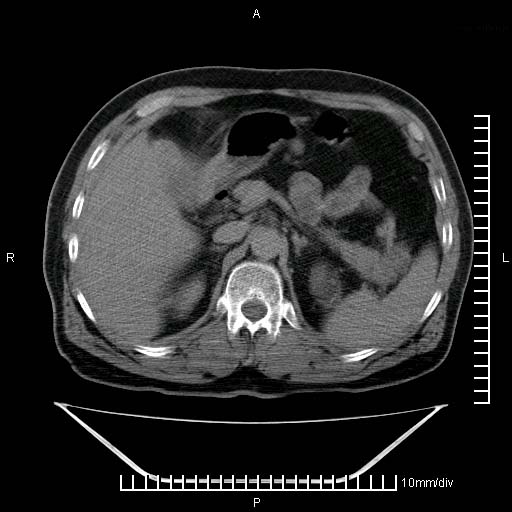

标题: CT25082:肝脏增强:男性,70岁 [打印本页]

标题: CT25082:肝脏增强:男性,70岁

患者以心脏疾病收住院,腹部无明显症状,b超查肝脏有占位。

肝内多发转移瘤,右下肺炎症并少量胸水。胃壁增厚建议胃镜,胰尾部“病变”为肠管。

1)肝脏多发性转移瘤(不排除胰尾癌转移所致可能)。2)腹水。3)右侧少量胸腔积液。

胰尾占位?结肠脾曲?

ct25082 结果:转移瘤

外院mr结果:胰尾恶性占位。